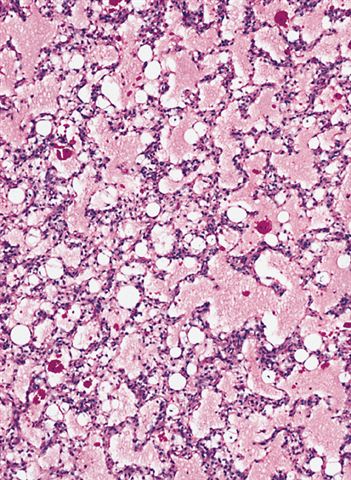

- High grade

- Hypercellular solid sheets of back to back cells with round cell or primitive cytomorphology in > 5% of the sampled tumor

- Cells can have a small amount of hypereosinophilic cytoplasm, a finding of no clinical significance but of significant diagnostic confusion, especially in a limited sample

- Pitfalls and tips

- High grade tumors are so cellular that you can typically walk across nuclei in a high power field without stepping in matrix